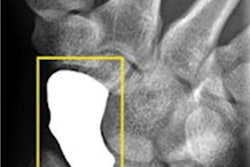

A 20-year-old man who had initial negative wrist and scaphoid radiographs. The follow-up radiograph (a) was normal. No fractures were observed in enlargements of the wrist radiographs and two scaphoid views (b). All images reprinted with permission of Springer Publishing.

Same patient above. With tomosynthesis (c), a nondisplaced scaphoid wrist fracture was observed in the dorsal cortex (arrows)."Even though we did not reach significance at the two-week follow-up, we still like the increased confidence we get from the addition of tomosynthesis to conventional radiography, and the extra fractures we keep finding," Geijer said.